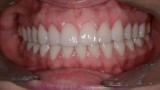

Następny etap leczenia polegał na adhezyjnym osadzeniu rekonstrukcji wykonanych z materiału E-max (Ivoclar, Liechtenstein). Po cementowaniu przystąpiono do preparacji zębów dolnego łuku zębowego. Pozostawienie wszystkich drugich zębów trzonowych w pierwotnym kształcie umożliwiło łatwą rejestrację pozycji żuchwy w RC przed rozpoczęciem preparacji, którą wykonano na twardym materiale (LuxaBite, DMG, Niemcy) (ryc. 32, 33). Po zakończeniu preparacji rejestrat zwarciowy powiększono o odcinek przedni, wykonano wyciski oraz zabezpieczono filary wcześniej przygotowanymi i podścielonymi uzupełnieniami z PMMA (ryc. 34-36). Podobnie jak w łuku górnym, w następnym etapie sprawdzono wewnątrzustnie prototyp rekonstrukcji wyfrezowany w PMMA, na którym wykonano niezbędne korekty zwarcia (ryc. 37, 38). Ostatni etap leczenia polegał na adhezyjnym cementowaniu rekonstrukcji dolnego łuku zębowego.

Ryciny 39-50 przedstawiają stan po zakończeniu leczenia.